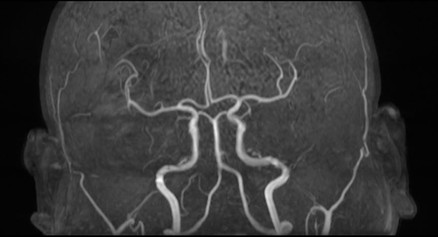

Brain and blood vessels (MRA of the brain)

Identify aneurysms, blockages, and vascular conditions